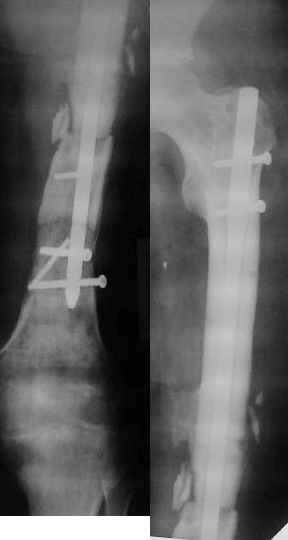

Здравствуйте, коллеги!!! К нам в отделение госпитализирован пациент 39 лет с клинико-рентгенологической картиной ложного сустава в/3 плечевой кости! Снимки прилагаются! Предистория такова: около года назад получил оскольчатый перелом в/3 плечевой кости. В одной из московских больниц выполнен остеосинтез пластиной, через несколько месяцев выполнен реостеосинтез, опять же пластной...., причины реостеосинтеза со слов пациента таковы - "доктору не понравилась как лежит пластина и он ее переложил..." - два месяца назад выполнено удаление фиксатора. Никаких выписок у больного нет. Около недели назад больной ударился областью плечевого сустава, появились боли, в связи с чем он обратился в травмопункт, откуда направлен к нам. Клинически у пациента имеется подвижность в области в\3 плеча, костная крепитация, умеренная болезненность в в/3 плеча при движениях, атрофия дельтовидной мышцы. На следующей недели планируем пациента опериравать. Коллеги, у нас возникло несколько вопросов, если не затруднит, то посоветуйте и подскажите... Мы планируем выполнить закрытый блокируемый остеосинтез, скажите пожалуйста, нужно ли в этом случае, на ваш взгляд, выполнять костную пластику или достаточно выполнить рассверливание костномозгового канала и заштифтовать толстым гвоздем, нужно ли пытаться удалить винты??? У нас в отделении идут дискуссии по этому поводу, придти к общему знаменателю не можем, поэтому и обращаемся к Вам!!! На основании ваших отзывов мы и примем окончательное решение!!! Спасибо!!! Очень ждем Ваших комментариев!!!

2. характер ложного сустава и состояние костных отломков: четкая рентгенологическая картина гипотрофического (аваскулярного) ложного сустава с выраженным склерозом концов отломков и значительным дефектом костной ткани диктует необходимость введения в область ложного сустава остеоиндутивного материала (если бы не было значительного дефекта и склероза концов отломков в межотломковую область можно было бы ввести костную крошку, полученную при рассверливании костномозгового канала). В данном случае значительный дефект кости и плохое состояние концов требует: а)«освежения концов отломков», б) введения в область ложного сустава васкуляризированого костного трансплантатата, либо свободного костного аутоторансплантата, либо выполнение дистракционного остеосинтеза («костного транспорта»). При этом Вам естественно придется «открывать» область перелома, а значит Вы легко удалите винты.

3. состояние костной ткани поврежденного сегмента: в данном случае костная ткань остеопорозна, с многочисленными «дырами» от винтов, ранее фиксировавших пластины. Поэтому фиксировать пластиной третий раза нецелесообразно. Остаются 2 метода: блокированный штифт для проксимального плеча (Т2 страйкер или аналоги), либо аппарат внешней фиксации (чем лучше владеете).

Провести штифт в дистальный отломок закрыто вряд ли удастся: «сосулькообразный» конец отломка, запаянный костномозговой канал, дополнительное препятствие в виде 2 винтов.